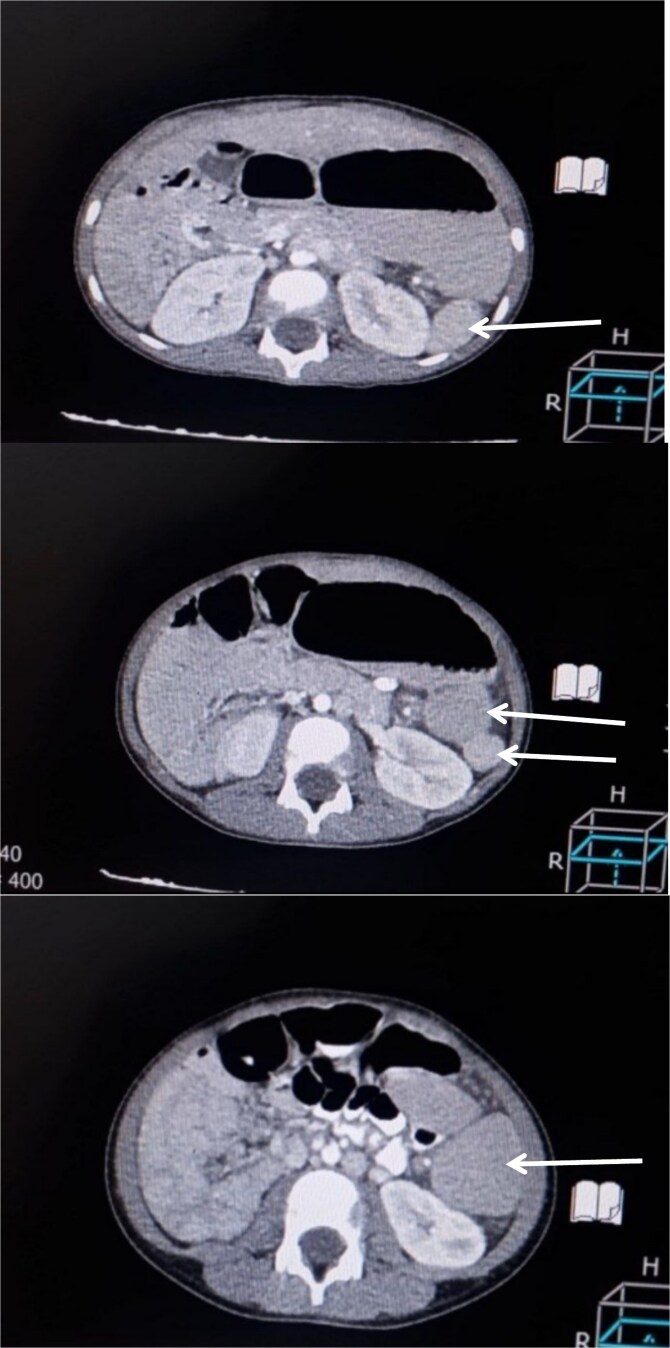

Acute abdominal pain in children presents a significant diagnostic challenge due to its broad differential, including rare congenital anomalies. Torsion of an accessory spleen is a rare but important cause, particularly in the context of polysplenia syndrome. We report the case of a 6-year-old boy with polysplenia syndrome who presented with severe abdominal pain, vomiting, and diarrhea. Imaging revealed multiple splenic masses, and exploratory laparotomy identified a torsed accessory spleen with a twisted vascular pedicle. Resection of the infarcted splenule and correction of associated intestinal malrotation were performed. The patient recovered uneventfully and was discharged on the third postoperative day. Splenic torsion in polysplenia syndrome should be considered in the differential diagnosis of acute abdomen in children with congenital anomalies. Prompt imaging and surgical intervention are essential for favourable outcomes, and increased awareness may aid in early diagnosis and management of this rare condition.

Abstract Image